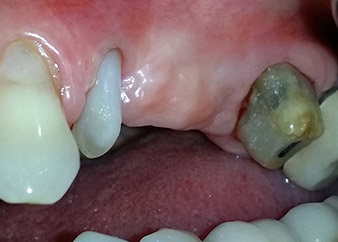

Figures 17 and 18 show the clinical result two months after the surgery. Tooth 24 exhibited reduced mobility of Miller class 1, and the soft tissues were free of inflammation. Probing was avoided at this point of time to prevent reinfection and to avoid violating the epithelial attachment. A control visit was scheduled for reentry and placement of healing abutments, six months after the insertion of the implants.

Two months after the surgery, the patient was pain-free.

Fig. 17: Two months after the surgery, the patient was pain-free and the area was free of inflammation.

after the surgery

Fig. 18: Tooth 24 now showed less mobility.